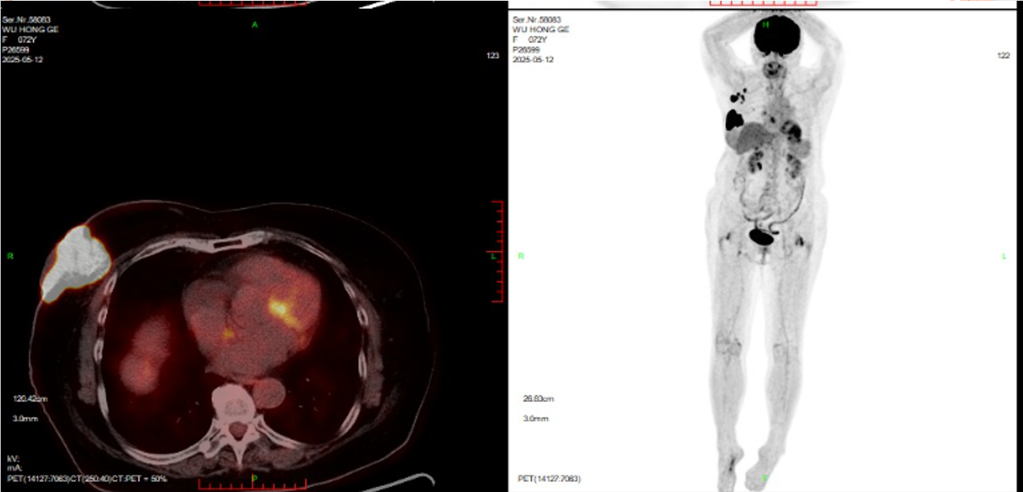

(2025-5-8)全身PET-CT检查:1.右侧乳腺外上象限软组织肿块,糖代谢增高,考虑乳腺癌,侵犯邻近右乳皮肤,与邻近右侧胸大肌可疑粘连,右乳头及乳晕、周围皮肤增厚,糖代谢增高,请结合临床。右侧腋窝多发高代谢淋巴结转移。2.双肺散在多发结节,糖代谢增高,考虑转移。